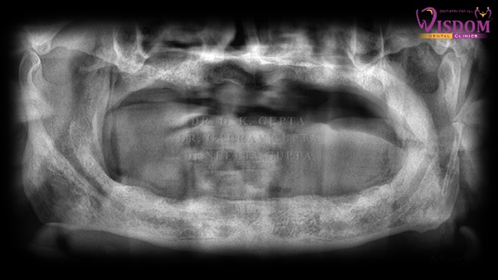

A complete case history was recorded following by thorough intraoral examination. Patient was adviced to undergo routine blood investigation, OPG and CBCT. [Figure 2a,2b]. Going through radiographical and clinical examination full mouth rehabilitation was planned with placement of short and bone level implants with final delivery of hybrid denture in order to get satisfactory results.

Figure 2a: Pre-operative OPG